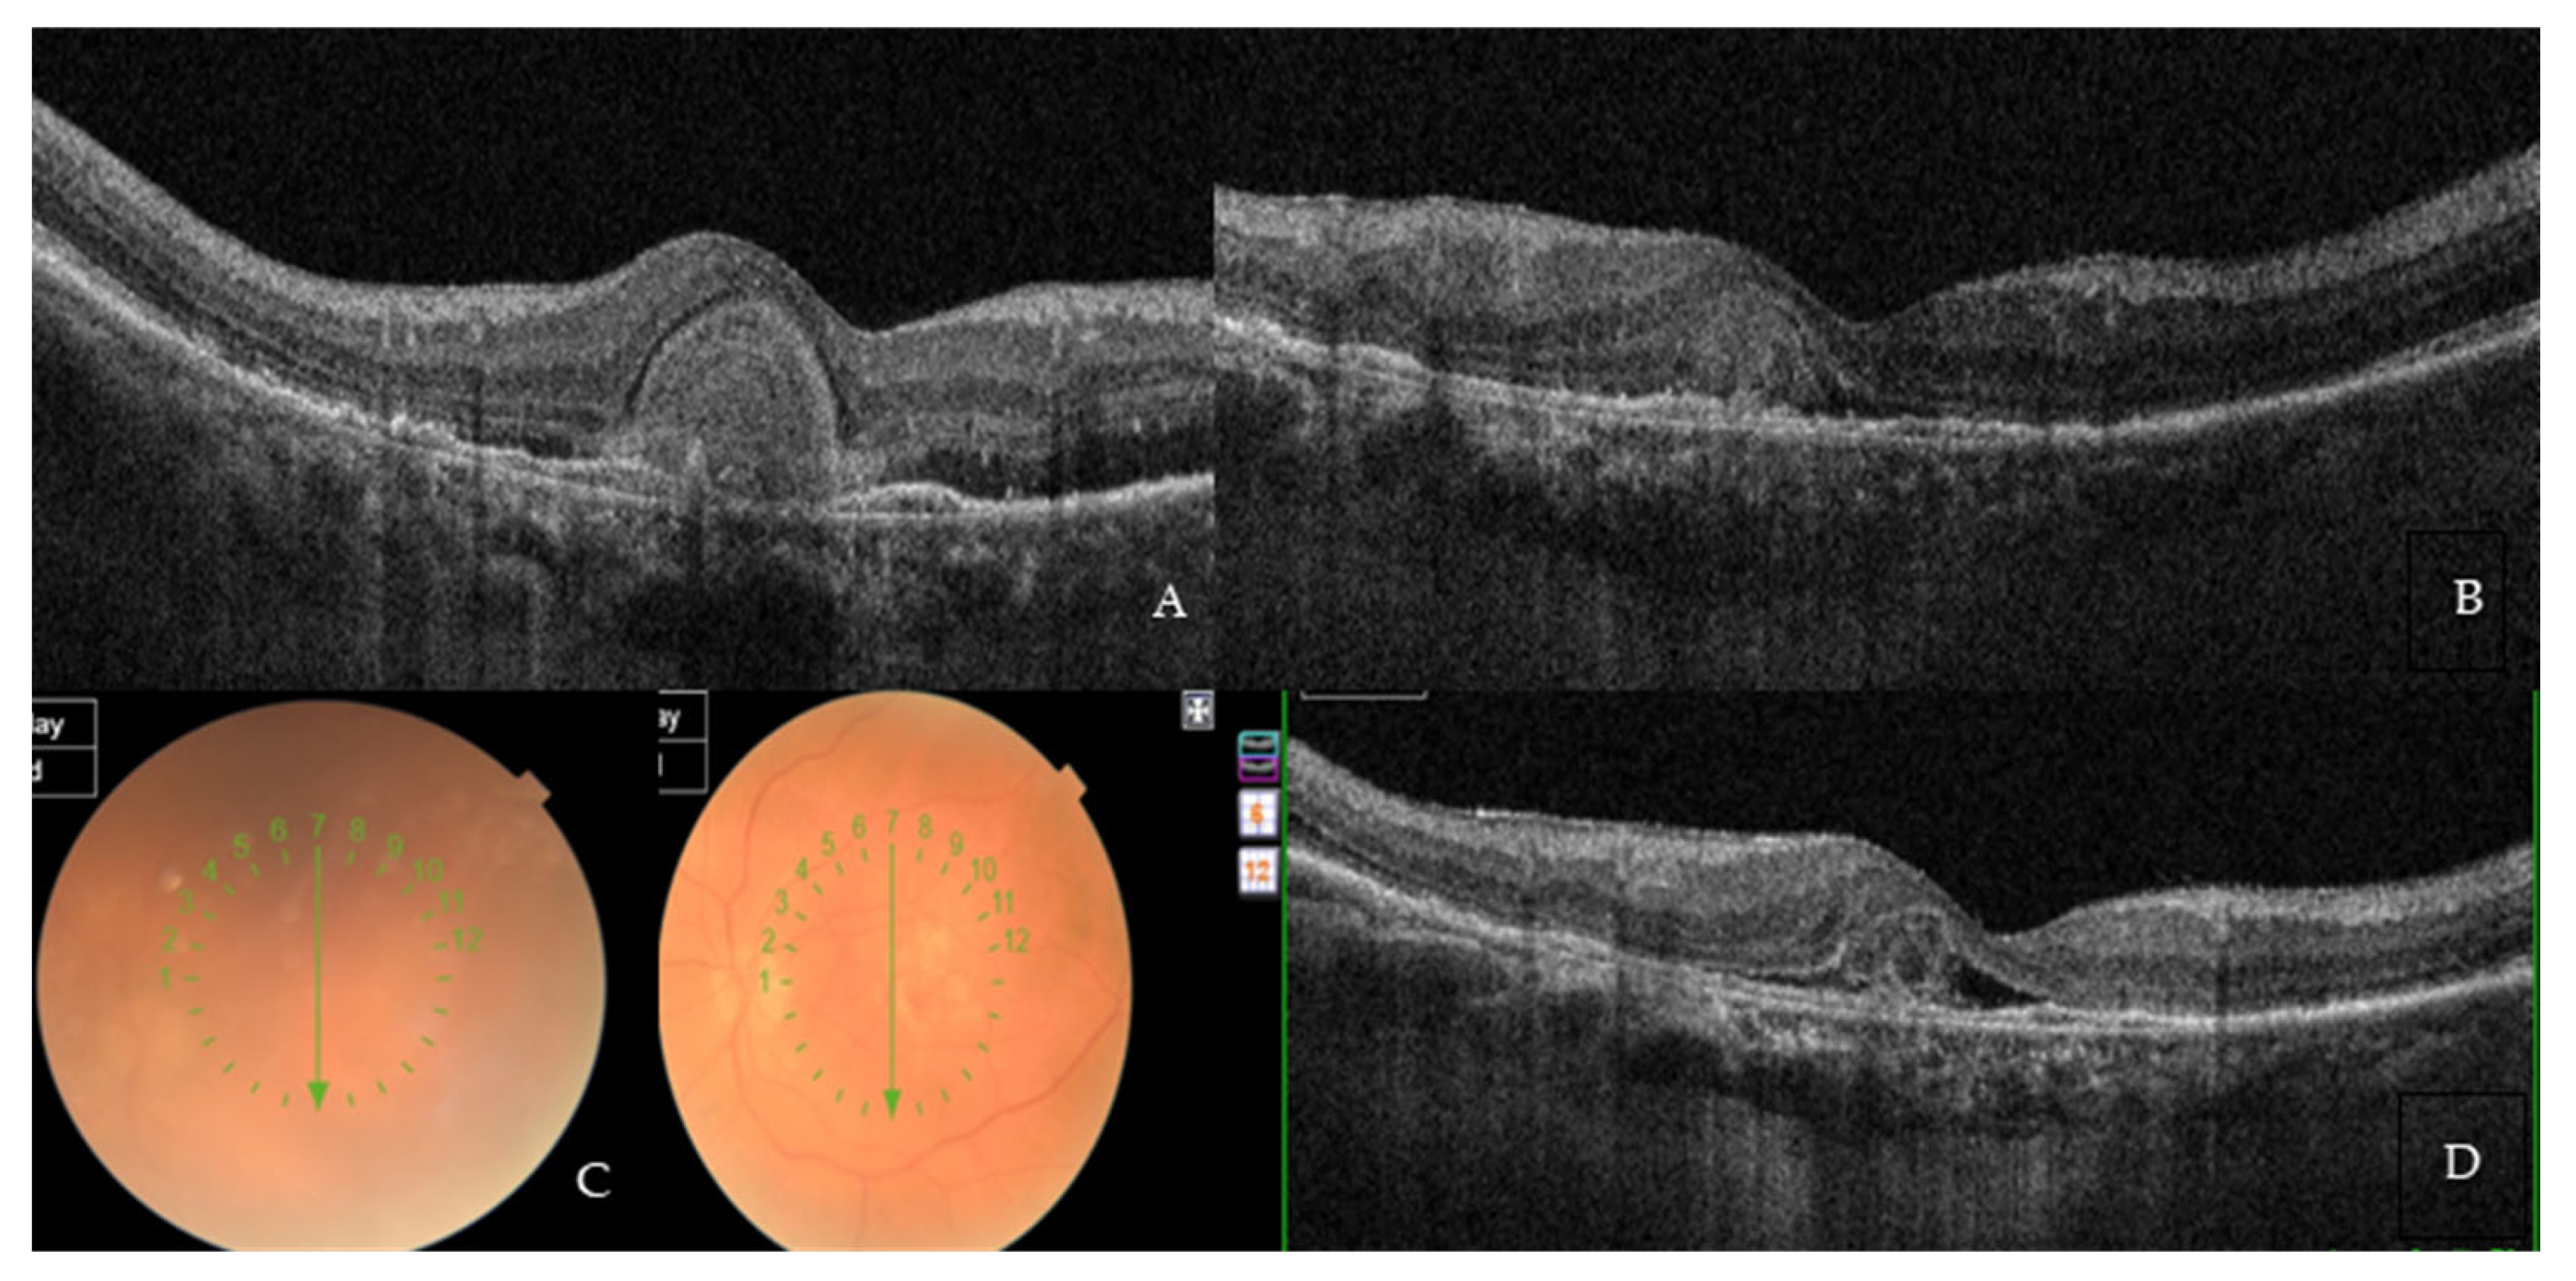

Two representative cases of patients from our cohort, before and after treatment with Brolucizumab, are shown in Figure 2A,B and Figure 3A,B.

Figure 2. (A) Baseline SD-OCT scan acquired with Maestro 3D OCT-1 (Topcon Corporation, Tokyo, Japan) of a non-treatment-naïve patient displaying diffuse intraretinal edema. (B) A 4-month SD-OCT scan acquired with Maestro 3D OCT-1 (Topcon Corporation, Tokyo, Japan) displaying subretinal hyper-reflective material and no residual edema.